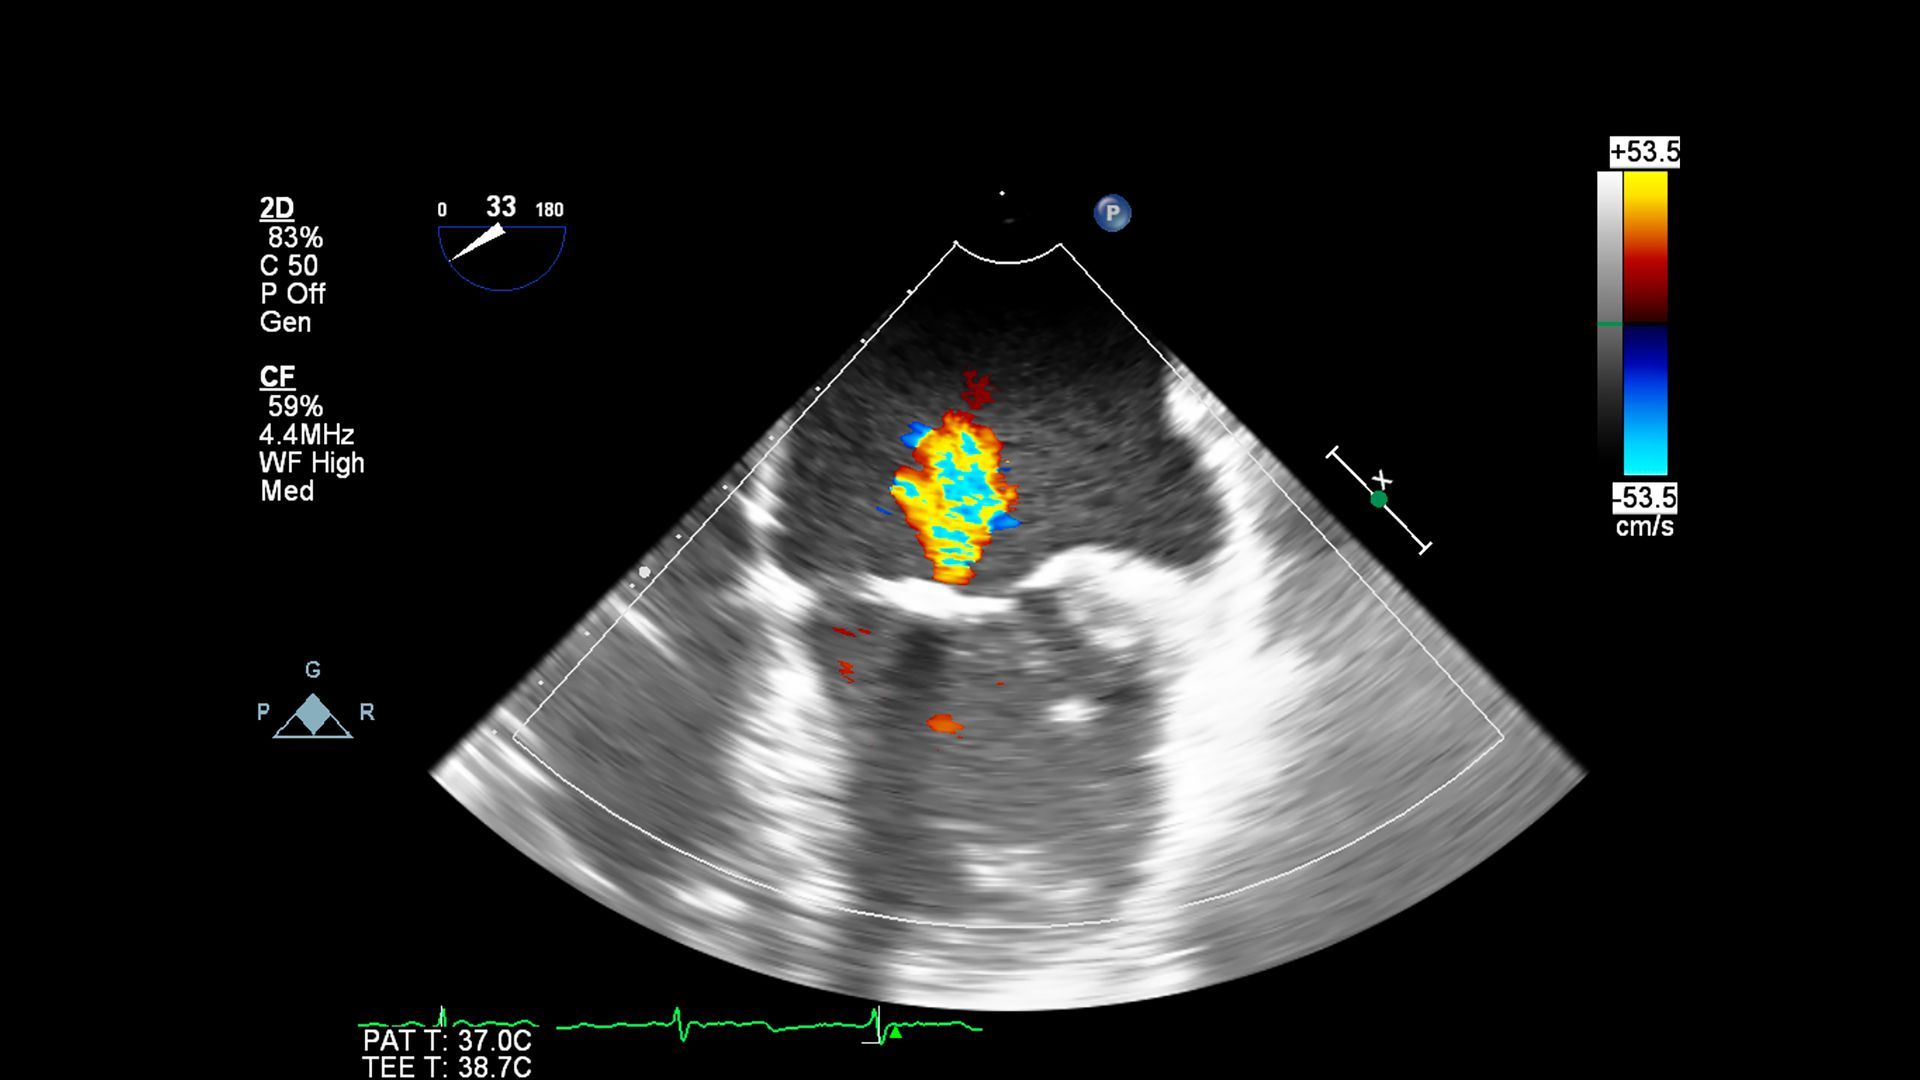

L’Ecocolordoppler è un’evoluzione dell’ecografia tradizionale, basata sull’utilizzo degli ultrasuoni per analizzare i tessuti molli e, in particolare, il sistema vascolare. La tecnologia Doppler permette di valutare il movimento del sangue, mentre la mappa colorimetrica integrata rende immediatamente visibili le zone in cui il flusso procede correttamente o presenta alterazioni.

Questo strumento diagnostico è particolarmente utile per monitorare la presenza di

placche aterosclerotiche, formazioni capaci di restringere il lume dei vasi, e per valutare il funzionamento del sistema venoso, specialmente nei casi di varici, reflusso venoso o trombosi. L’esame non utilizza radiazioni ionizzanti e non richiede alcuna preparazione, risultando adatto a pazienti di ogni età.